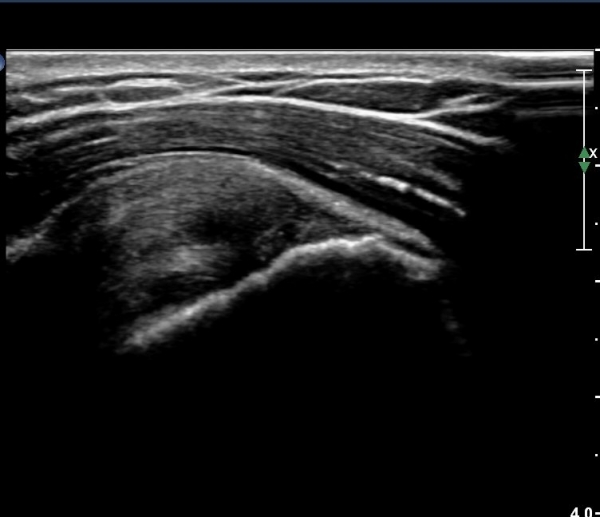

ȸÀü±Ù°³°£°Ý(rotator cuff interval) Ⱦ´Ü¸é°Ë»ç¿¡¼­ °ß°©ÇϱٰǻóºÎ¿Í ±Ø»ó°Ç ³»ÃøºÎ¿¡

ƯÀÌ ¼Ò°ßÀ» º¸ÀÌÁö ¾Ê´Â´Ù(»çÁø 1, 2).

¿À±¸µ¹±â°ßºÀÀδë Á¾´Ü¸é°Ë»ç¿¡¼­ Àδ밡 Á¤»óÀûÀ¸·Î °üÂûµÇ°í(»çÁø 4)

°ßºÀ¿¡ À§Ä¡ÇÑ  ŽÃËÀÚ¸¦ ¾à°£ ¸»´Ü(caudal)À¸·Î À̵¿ÇÏ´Ï °ßºÀ ¾Æ·¡Ãø¿¡¼­ ³»ÃøÀ¸·Î °í¿¡ÄÚ ¼®È¸È­À½¿µÀÌ °üÂûµÈ´Ù(»çÁø 5).